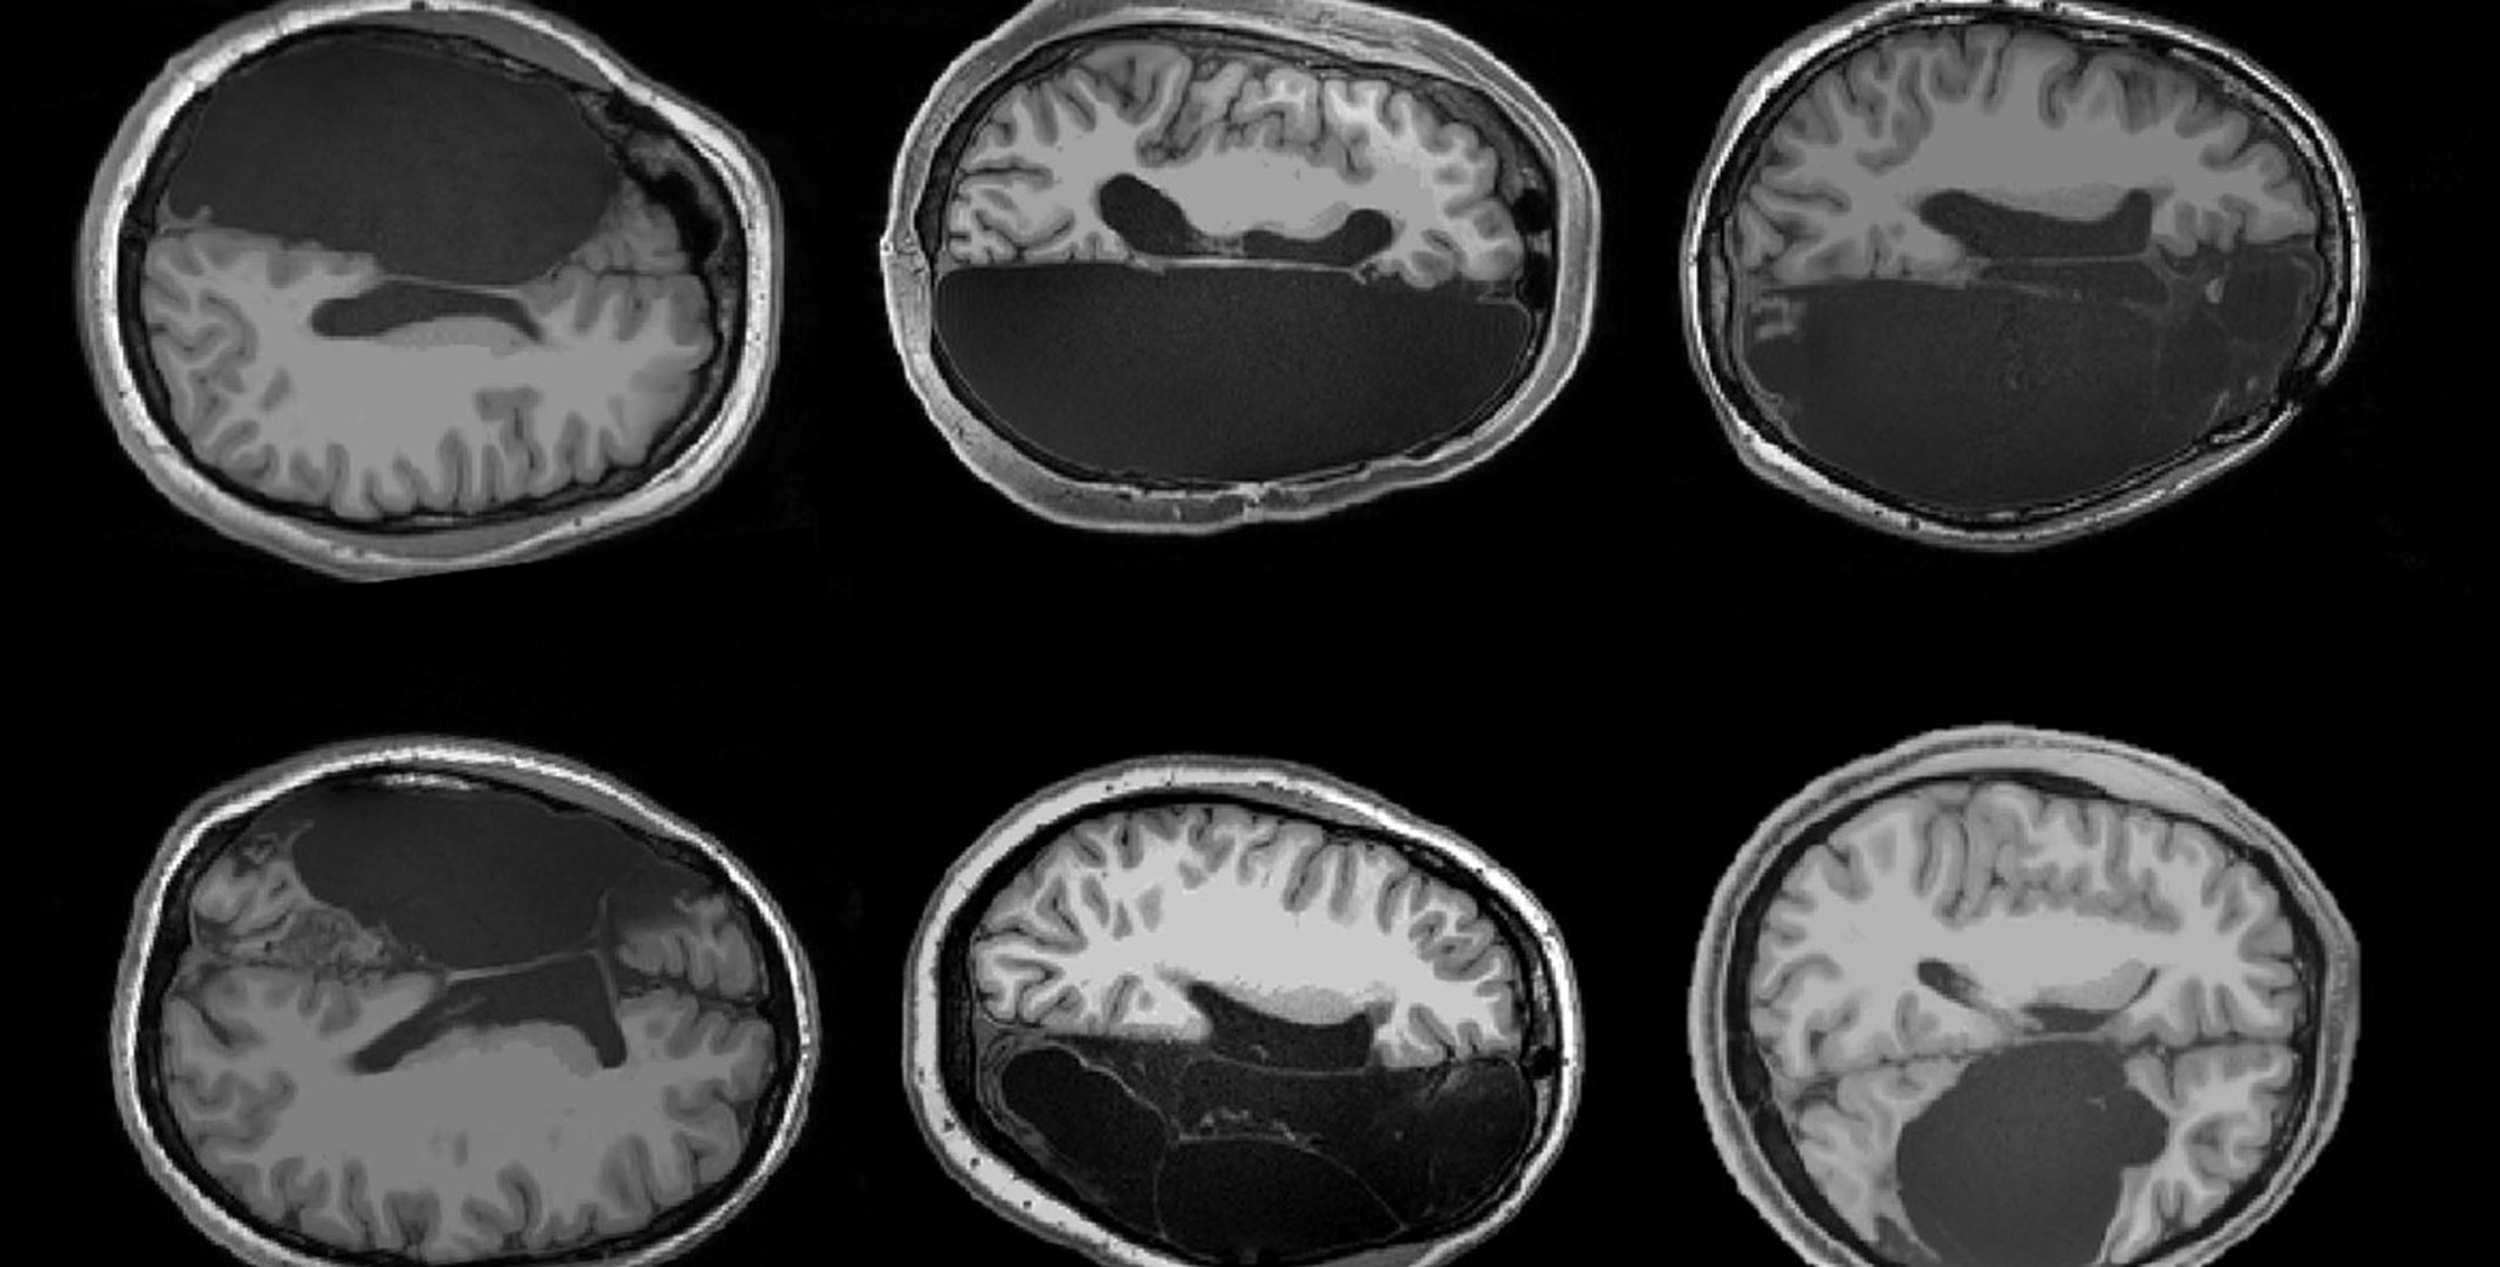

En un artículo reciente publicado en la revista Neuropsychologia se menciona el caso de una mujer que un día, durante un chequeo médico, descubrió que le faltaba el lóbulo temporal izquierdo. Esta región, normalmente, desempeña una función importante en la capacidad para entender lo que se nos dice. Este tipo de ausencia debería suponer algún tipo de limitación en las habilidades lingüísticas de la paciente, pero ella nunca las había experimentado y jamás había intuido que algo faltase en su cerebro.

Casos como este no son tan extraños y en muchas ocasiones tienen que ver con defectos congénitos que producen accidentes cerebrovasculares en las fases tempranas del desarrollo. De hecho, según recogía un artículo en la revista Wired, a la hermana de la paciente analizada en el trabajo publicado en Neuropsychologia le falta el lóbulo temporal derecho. Pero la naturaleza, con esa especial habilidad para adaptarse a las circunstancias, permitió a las dos hermanas tener una vida normal, reorganizando el cableado de su cerebro para colocar las funciones del lenguaje en las partes intactas.

Javier de Felipe, investigador del Instituto Cajal del CSIC, en Madrid, comenta otros casos de personas sorprendidas por sus particularidades cerebrales, como el de un hombre que por un caso de hidrocefalia durante la infancia “tenía agua en el cerebro y la corteza reducida a una pequeña lámina”, y aun así llevaba una vida normal, “o individuos que viven prácticamente sin cerebelo”. Sin embargo, apunta, “esas alteraciones sucedieron en las primeras etapas de la vida, cuando es posible que gracias a la plasticidad del cerebro, otras regiones intactas suplan las funciones dañadas”. Cuando este tipo de lesiones se producen en edades más avanzadas, el resultado es catastrófico.